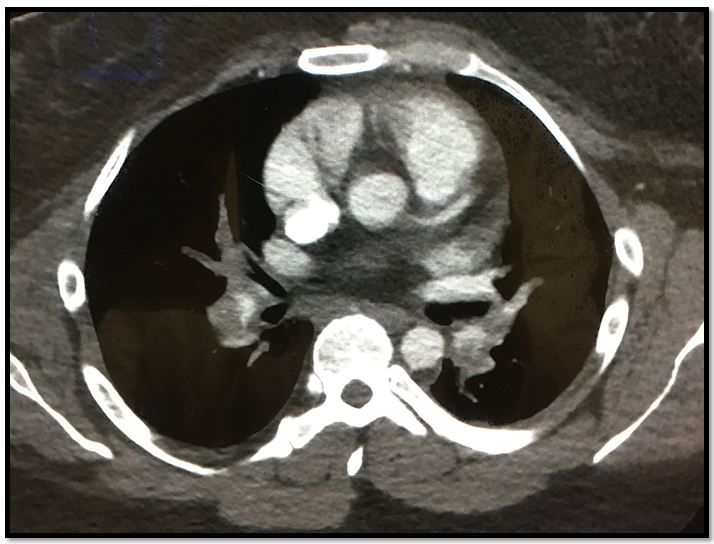

What should you do next? Order a CT chest to evaluate for PE. It was positive for multiple large PEs (see Figure 2, at right; please click to enlarge).

This patient was more at risk for PE than ACS so a D-dimer was also ordered, which was elevated. A CT angiograph showed multiple bilateral PEs. Although in some studies approximately 20% of painful PEs have nonpleuritic pain, that estimate is likely high. In my experience painless PEs are far more common than nonpleuritic PEs. Remember, larger or multiple PEs can cause a variety of findings that suggest ACS or CHF. These include “ischemic” ECG changes and elevations of BNP and/or troponin. Sometimes it’s not enough to diagnose chest pain and admit. Sometimes you need to know when to keep looking rather that prematurely “close the case.”